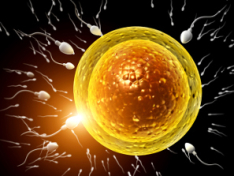

La infertilidad del varón suele deberse a un escaso número de espermatozoides en el semen o a su falta de movilidad y, según los estudios científicos, ha aumentado en los últimos años. Los tóxicos ambientales, la contaminación y el consumo de alcohol o tabaco provocan que los hombres...

Implantación del embrión, el milagro

La implantación embrionaria es uno de los mayores misterios del embarazo, ya sea espontáneo u obtenido mediante técnicas de reproducción asistida. Si fracasa, no hay gestación posible. Aunque el organismo materno sea capaz de liberar un óvulo maduro. Aunque se produzca el milagro de la...